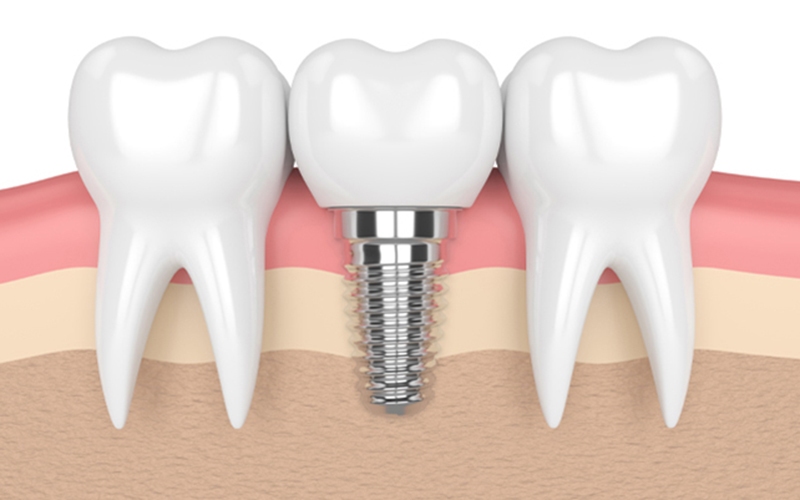

インプラント治療とは、歯を失った部分に人工の歯根を埋め込み、その上に人工の歯を装着する治療法です。従来の入れ歯やブリッジと異なり、隣の歯に負担をかけることなく、天然の歯と同じような感覚でしっかり噛むことができるのが特徴です。

お口の中が清潔で炎症のない状態であることを確認したうえで、手術を行います。局所麻酔を施し、顎の骨にインプラント(人工歯根)を埋め込みます。このインプラントが、新しい歯の土台となります。

インプラントが骨としっかり結合することで、強い噛む力を支えられるようになります。

インプラントが顎の骨としっかり結合したら、その上に「アバットメント」と呼ばれる人工歯を支える土台を取り付けます。その後、セラミックなどで作られた人工の歯(上部構造)を装着します。